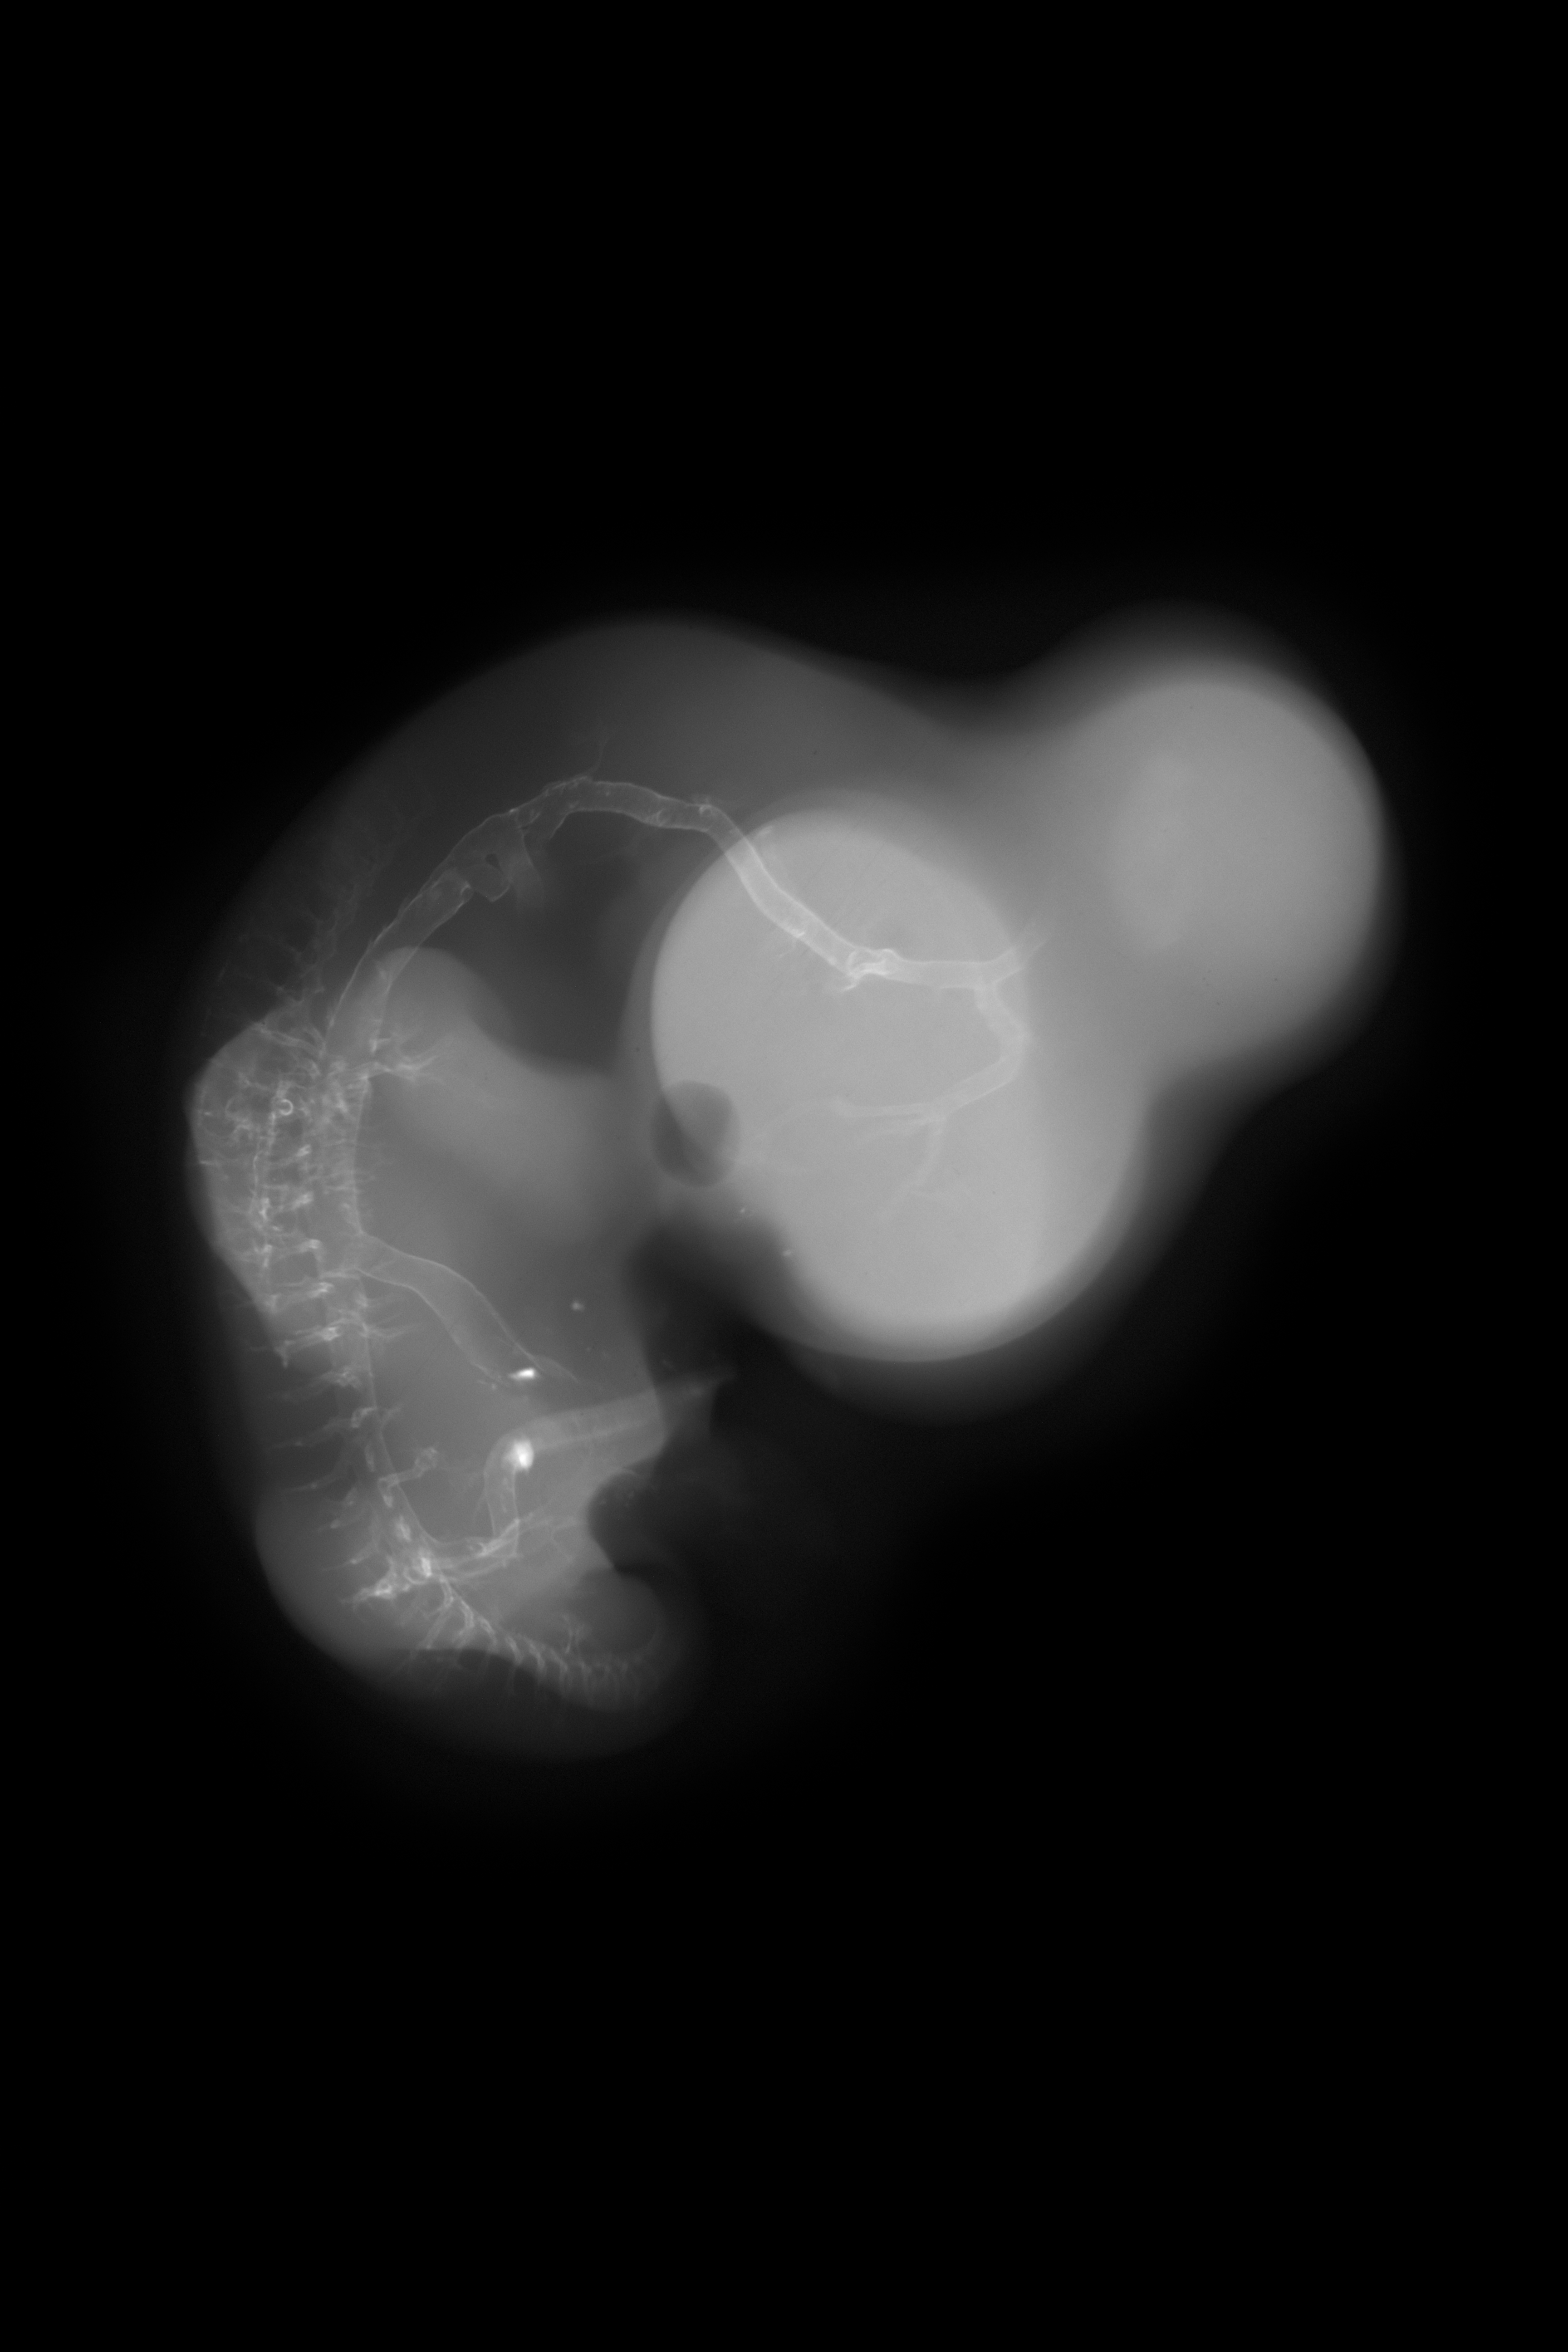

Chick Embryo Microangiography

Hamburger-Hamilton (HH) Stage 28 (approx. 5.5 - 6 days)

X-Ray Micrographs